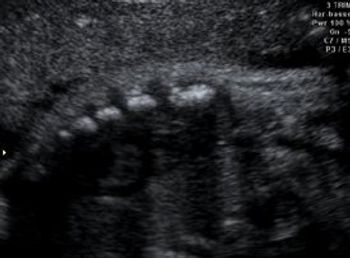

Normal 35 week pregnancy